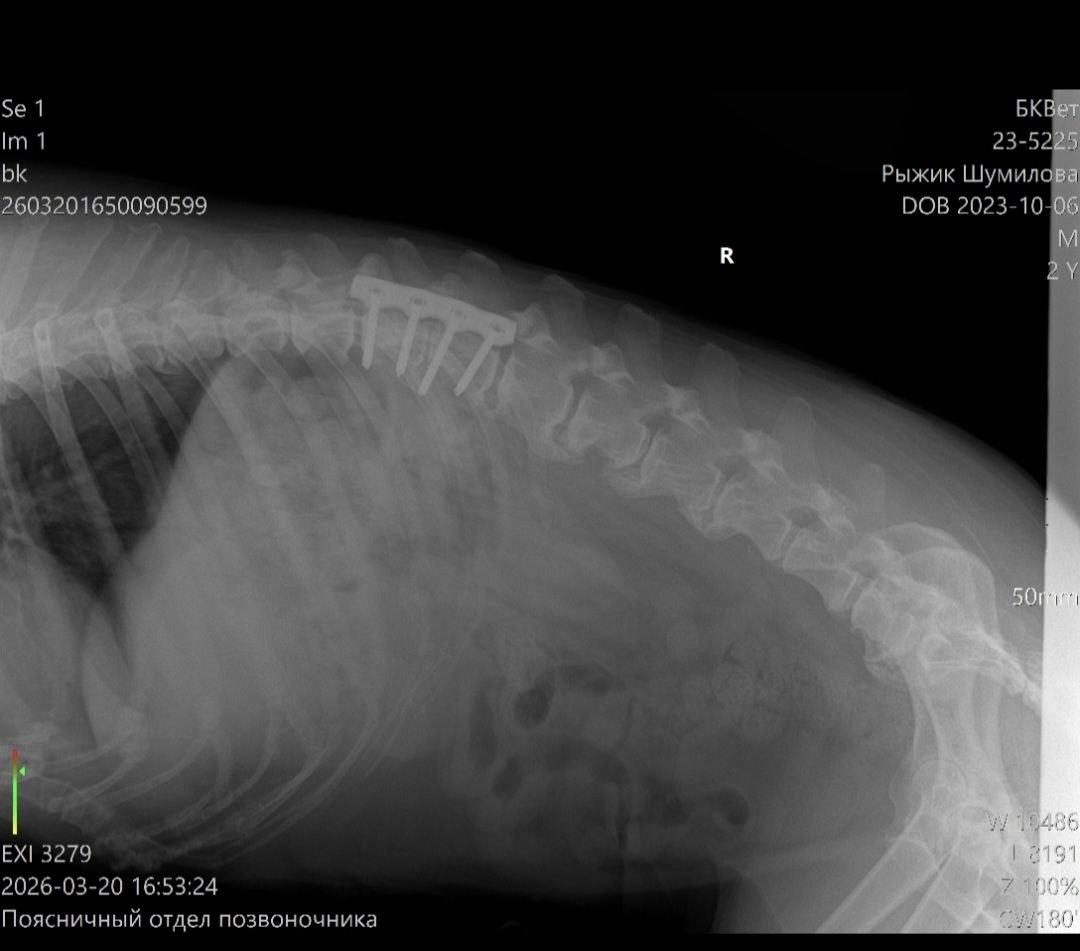

Дорогие друзья, Рыжик был на приеме у хирурга -ортопеда

Дорогие друзья, Рыжик был на приеме у хирурга -ортопеда. Доктор отправил бедолагу на КТ ( для детального исследования) .